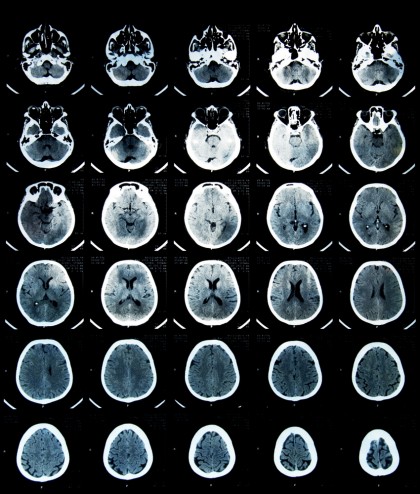

- Analiză imagistică TSPO PET pe o cohortă separată de 114 pacienți, incluzând 1.326 de leziuni albe cerebrale.

Leziunile au fost clasificate ca active, mixte sau inactive, iar remielinizarea a fost evaluată semiquantitativ. BRLs au fost definite histologic printr-o margine perilezională extinsă de macrofage și microglie (>1 mm), iar imagistic (rBRLs) prin prezența unei zone periferice cu activitate inflamatorie crescută în PET.

Corelații imagistice

- TSPO PET a identificat BRLs radiologice (rBRLs) în 34% dintre pacienți, reprezentând 10% din leziunile evaluate.

- Proporția de rBRLs a fost asociată cu:

- activare microglială difuză în materia albă aparent normală (NAWM),

- scăderea anizotropiei fracționare și creșterea difuzivității medii în DTI, indicând deteriorare difuză.

- Pacienții cu rBRLs au avut un risc crescut de a atinge EDSS 4 sau 6 în 12 ani de la debut.

Detectarea in vivo prin PET TSPO confirmă fezabilitatea utilizării BRLs ca biomarker imagistic, complementar RMN-ului clasic, și deschide calea pentru o monitorizare mai precisă a inflamației cronice în SM.